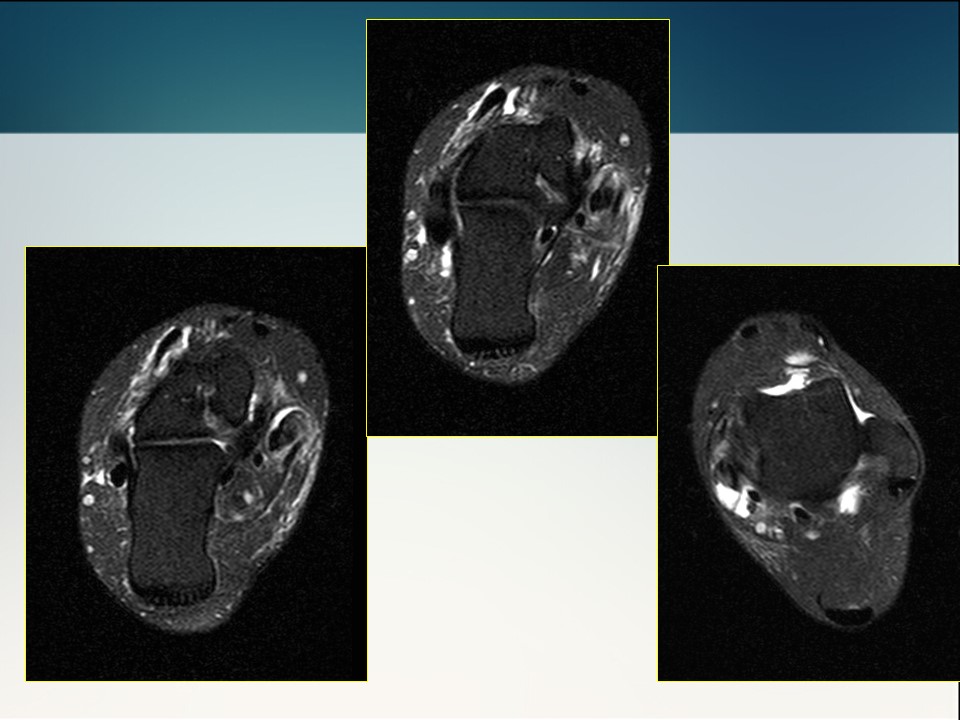

半月板损伤术前及修补术后MR影像学评价